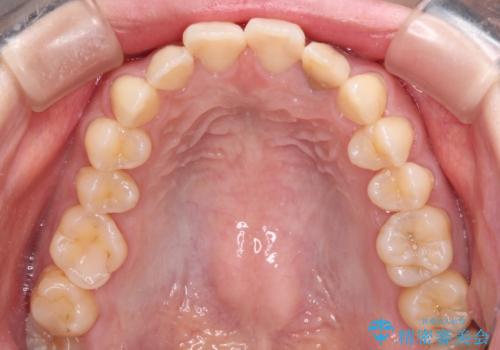

根管治療はやり直さずに、ファイバーポストを使用した土台を植立してオールセラミッククラウンにて補綴することとしました。

クリーニングやホワイトニングでは改善できないため、オールセラミッククラウンなどによる補綴治療が必要となります。